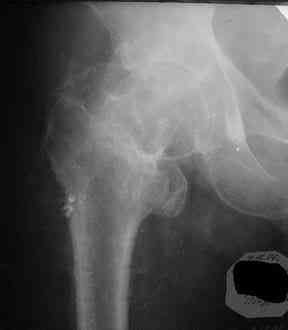

При удалении (наркоз) после неимоверных усилий пришлось выкрутить фиксатор единым блоком и только тут все встало на свои места. См. фото.

Грустно+ Вот какие сюрпризы преподносят иногда коллеги.